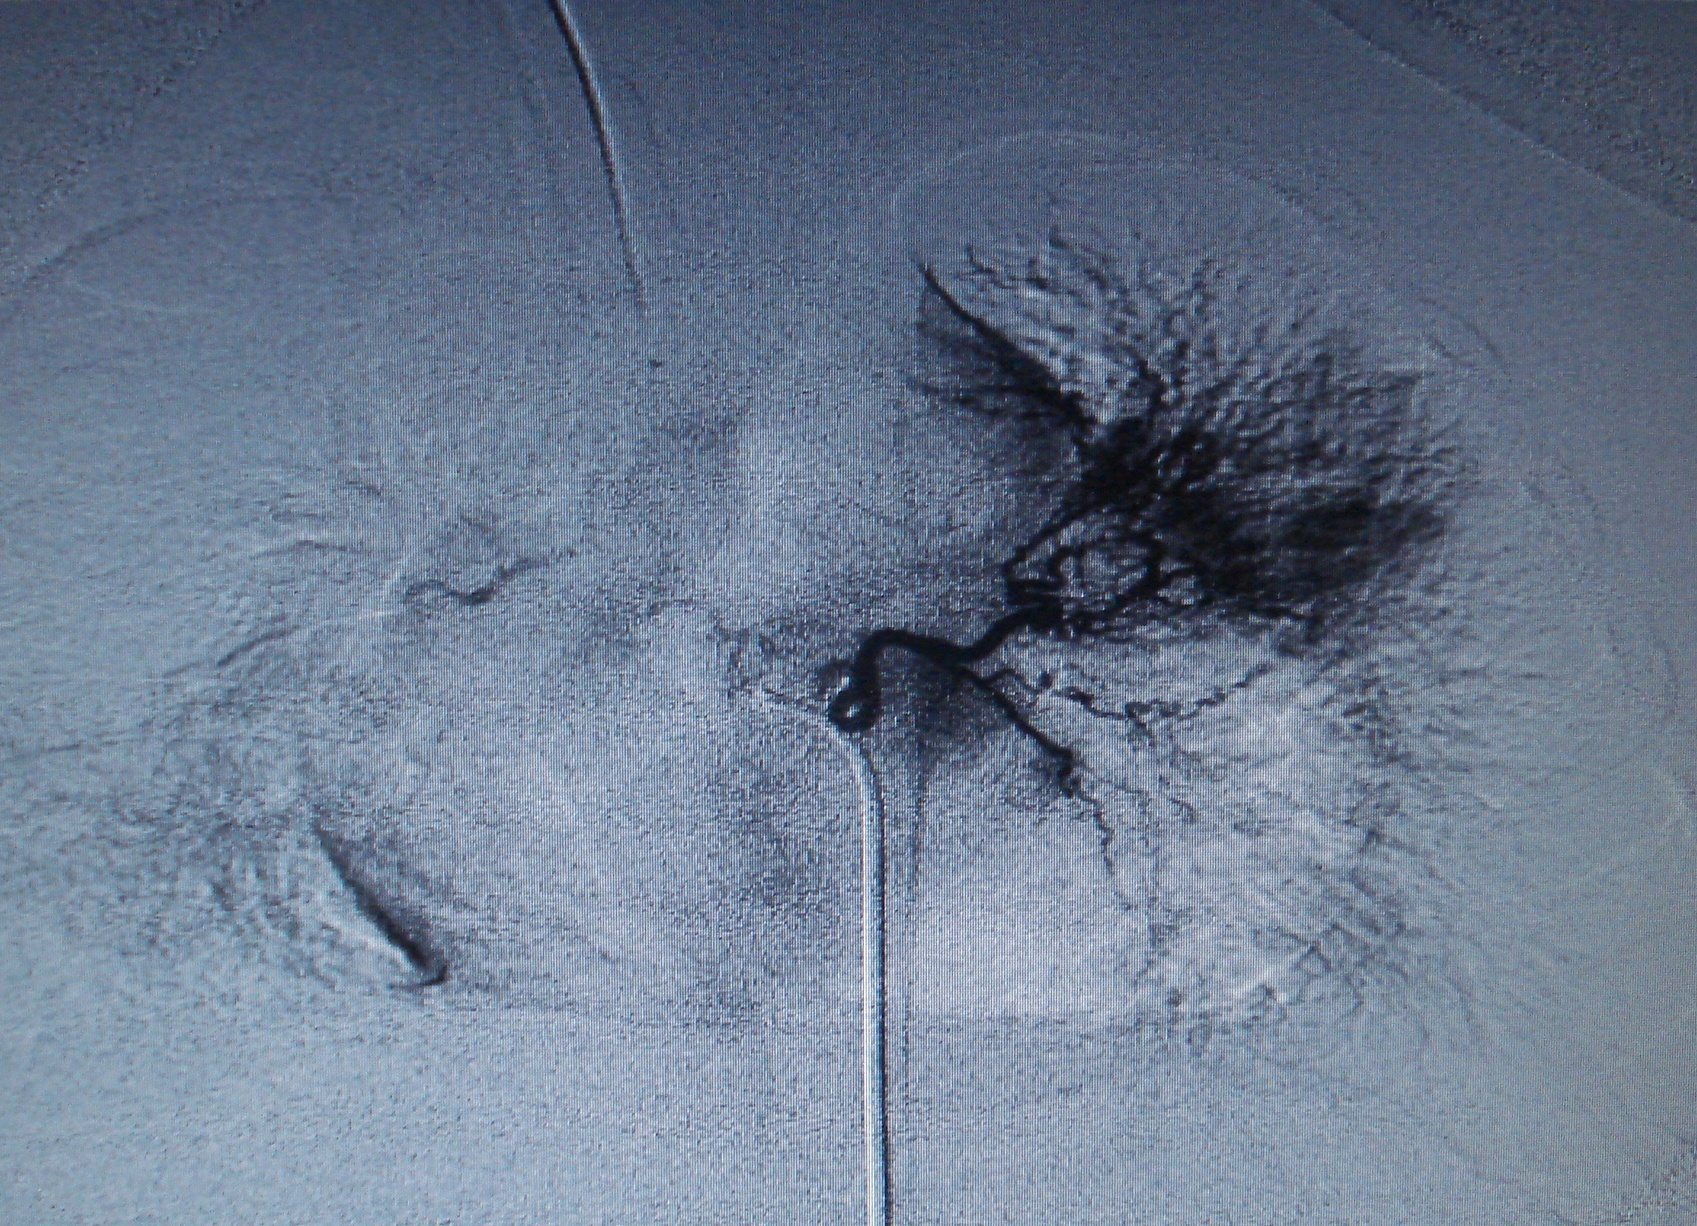

Paciente de 1 año y seis meses, con antecedentes de infecciones respiratorias recurrentes localizadas y hemoptisis. Mediante angiografía de la arteria pulmonar y de las ramas bronquiales de la aorta descendente se diagnostica estenosis de venas pumonares con colaterales aortopulmonares.The magazine does not retain the reproduction rights (copyright) so the authors can republish their works with the sole mention of the original publication source.